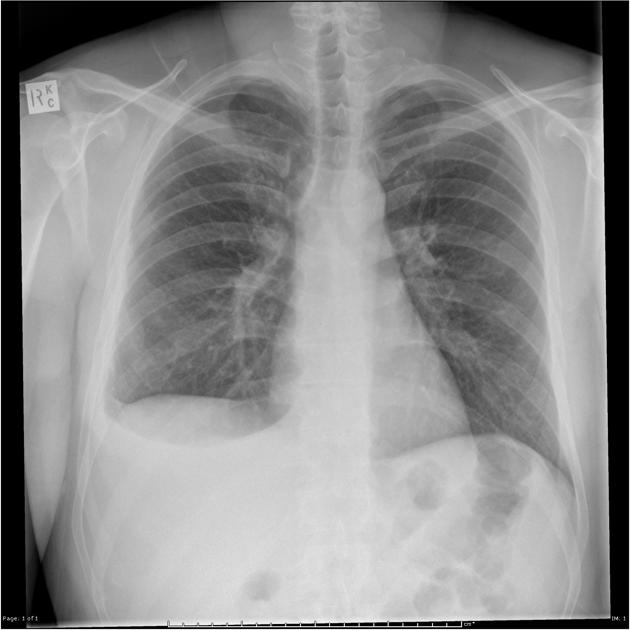

Describe the abnormality demonstrated.

Enlarged heart, Kerley B lines at both lung bases, left-sided pleural effusion, subtle cephalisation - all in keeping with congestive heart failure